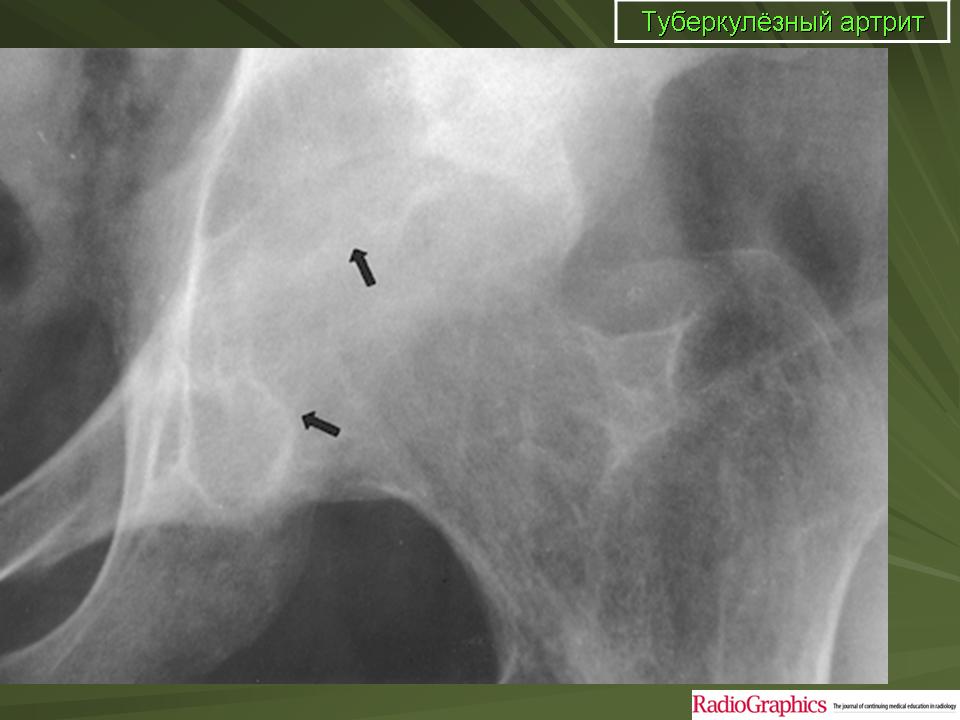

Туберкулез тазобедренного сустава (коксит)

Поражения тазобедренного сустава также относятся к одной из частых локализаций костно-суставного туберкулеза и на его долю приходится около 20% случаев поражений костей при туберкулезе.

Если раньше считалось, что почти 60% случаев приходится на детей первого десятилетия жизни, то в настоящее время туберкулез тазобедренного сустава стал относительно часто встречаться у лиц старшего возраста.

Ранние клинические проявления специфического поражения тазобедренного сустава незначительны. Это хромота, которая сначала возникает периодически, а затем, через 2—3 месяца,

становится постоянной. Боли носят непостоянный характер. Постепенно появляется ограничение движений и у детей возможно удлинение конечности.

При рентгенологическом исследовании в преартритической фазе самым ранним симптомом является остеопороз, который может быть незначительным и выявляться лишь на сравнительных рентгенограммах с захватом двух тазобедренных суставов. Еще до появления туберкулезного остита могут отмечаться изменения со стороны мягких тканей в виде увеличения теней межмышечных прослоек между контурами суставной сумки и малой и средней ягодичными мышцами (симптом Ланге — Будинова). Отмечается также асимметрия костей малого таза (симптом Пинхасика), обусловленная неправильным положением больного из-за атрофии мышц, или наоборот утолщением сустава на больной стороне, или вследствие болевой контрактуры. Зная наиболее частую локализацию туберкулезных оститов вокруг тазобедренного сустава можно выявить участки нарушения костной структуры, нечеткость костных трабекул. Спустя 1,5—2 месяца выявляются очаги деструкции костной ткани с нечеткими неровными контурами, которые могут содержать множественные губчатые секвестры. Наиболее часто туберкулезные оститы располагаются в костях, образующих вертлужную впадину, реже они встречаются в шейке, и как исключение в головке бедренной кости. Причем очаги деструкции костной ткани, расположенные в вертлужной впадине, лучше выявляются на задних рентгенограммах, а очаги деструкции в шейке бедра, особенно в нижне-внутреннем отделе ее лучше выявляется на рентгенограммах с отведением бедра (по Лауенштейну). У некоторых больных наблюдается ранняя деформация ядра окостенения головки бедра в виде его увеличения.

При переходе процесса на сустав клинические симптомы становятся постоянными и выраженными. К болям присоединяется сгибательная контрактура, усиливается атрофия мышц бедра. Натечные абсцессы могут выявляться в передне-наружном отделе бедра, реже в области ягодичных мышц.

Артритическая фаза (при переходе процесса на сустав) на рентгенограммах характеризуется усилением остеопороза, который постепенно распространяется на все кости нижней конечности. Суставная щель асимметрично суживается, больше в верхне-наружных отделах. В дальнейшем сужение суставной щели достигает значительной степени. Суставные поверхности костей теряют свои очертания, их контуры становятся нечеткими, неровными. Выявляются краевые, без четких контуров содержащие секвестры, очаги деструкции костной ткани. Последние могут вызывать значительные разрушения вертлужной впадины, головки и даже шейки бедренной кости, смещение головки бедра вверх.